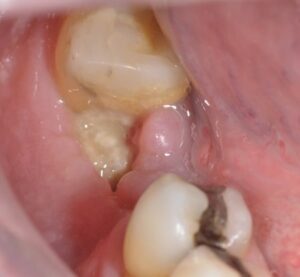

رشد غیرطبیعی استخوان (Exostosis Tori)

رشد اضافی استخوان، که به آن اکسوستوزیس میگویند، میتواند باعث بیرون زدگی شود، این رشد معمولا در قسمت داخلی فک پایین (mandibular) یا فک بالا پیش میآید و بدون درد است.

دلایلش ژنتیکی یا به خاطر فشار مداوم است، اغلب در بزرگسالان دیده میشود و نیاز به درمان ندارد، مگر اینکه باعث پارگی لثه شود.